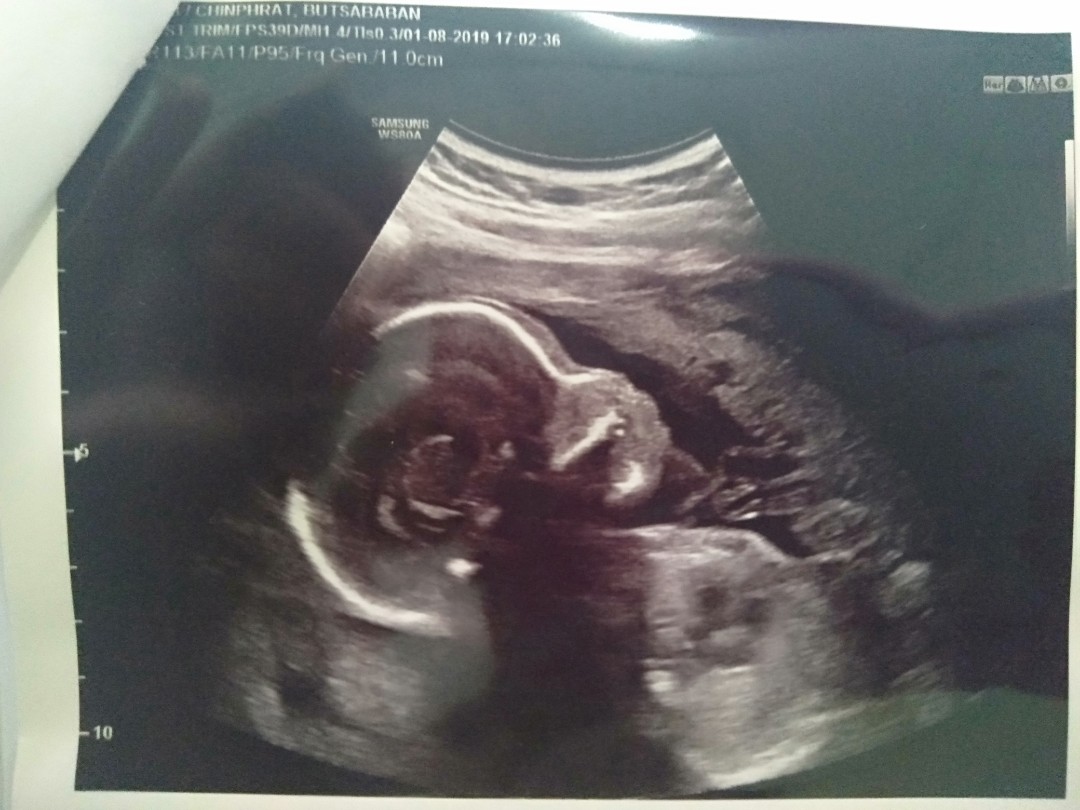

แม่บ้านนี้อยากได้ลูกสาวค่ะ #กำหนดคลอด 12 ธันวาคม #รูปซาวด์ตอน 12W